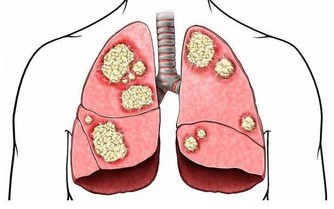

目前,在一線大城市,腸癌有超越肺癌成為新“癌王”的勢頭。今年發布的《中國體檢人群結直腸癌及癌前病變白皮書(2020年版)》指出,結直腸癌是我國高發癌症,2015年,中國新發患者38.8萬例,死亡約18.7萬例。換言之,平均每10分鐘,約7人被診斷為結直腸癌,約4人因此去世。這也為我們敲響警鐘,應當學會腸癌的預防。腸癌有沒“光臨”你,摸摸這處就知道!